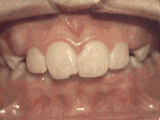

Apiñamiento de dientes

El paciente inició su tratamiento a la edad de 11 años y usó frenos por 26 meses. Está muy feliz con su nueva sonrisa.